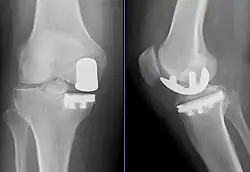

![]() Radiographs of a knee arthroplasty of the medial compartment | |